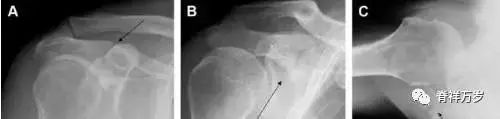

单纯肱骨大结节骨折

与其它肱骨近端骨折不同,单纯肱骨大结节骨折常发生于年轻人。肱骨大结节骨折常由撞击或剪切/撕脱损伤所致:

撞击包括直接撞击、肩峰撞击、上关节盂撞击(极度外展时);

剪切/撕脱损伤常发生于肩关节前脱位。

在常规前后位片上,大结节与肱骨头重叠,骨折不易发现,外旋位前后位片有助于诊断。

图 1 大结节骨折。(A)脂肪抑制序列斜冠状位 MRI,显示肱骨大结节线性骨折无移位(箭头)与周围骨水肿;(B)外旋位前后位(AP)片,证实大结节骨折(箭头),典型的骨折愈合过程中的骨吸收表现;(C、D)初诊时内旋位、外旋位前后位片,初诊时漏诊,仔细回顾影像,内旋伞下可见双密度影(椭圆),骨皮质中断(箭头)。